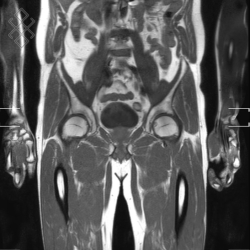

IRM Corps Entier

Vous entrez dans l'aimant, ouvert des 2 côtés, la tête la première et allongé sur le dos. Pour recueillir le signal et construire les images, vous aurez des antennes sur tout le corps. Étant donné que cet examen est bruyant, vous aurez un casque sur les oreilles pour atténuer le bruit de la machine.

La durée moyenne de l'examen est de 45 min. Vous entendrez un bruit caractéristique à l'IRM faisant penser à un marteau piqueur.